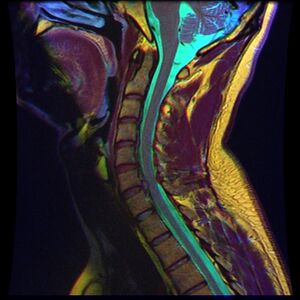

الانزلاق الغضروفي العنقي

يحدث الانزلاق الغضروفي العنقي، غالبًا بين الفقرات العنقية الخامسة والسادسة (C5–6) والسادسة والسابعة (C6–7). هناك قابلية متزايدة بين المرضى الأكبر سنًا (60+) للفتق في الجزء العلوي من العنق، وخاصة في الفقرات العنقية الثالثة والرابعة.[23] قد تظهر أعراض الانزلاق الغضروفي العنقي في الجزء الخلفي من الجمجمة والعنق وحزام الكتف ولوح الكتف والذراع واليد.[24] قد تتأثر أعصاب الضفيرة العنقية والضفيرة العضدية.[25]